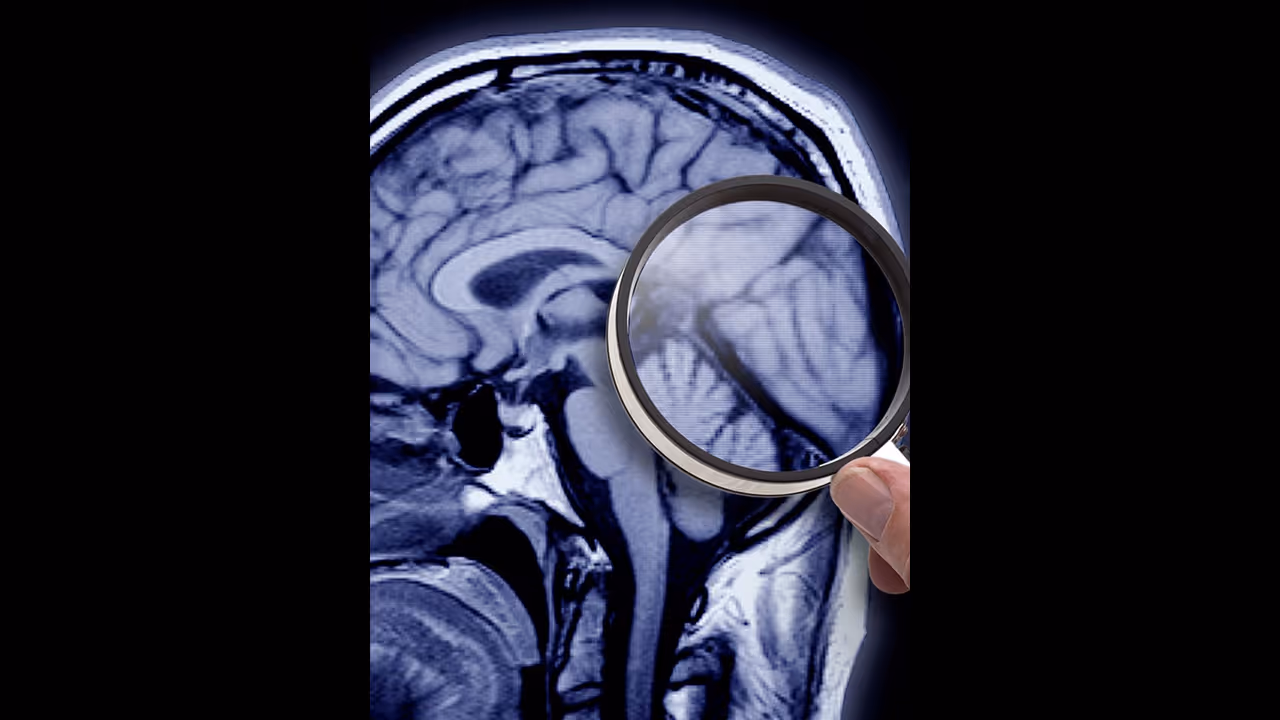

അല്ഷിമേഴ്സ് രോഗത്തെ കുറിച്ച് ഇന്ന് ധാരാളം പേര്ക്ക് അവബോധമുള്ളതാണ്. നമ്മുടെ തലച്ചോറിനെ ബാധിക്കുന്നൊരു രോഗമാണിത്. പ്രധാനമായും മറവിയാണ് അല്ഷിമേഴ്സ് രോഗത്തിന്റെ വലിയൊരു പ്രശ്നം. പതിയെ പതിയെ ആയി രോഗി എല്ലാം മറന്നുപോകുന്ന അവസ്ഥയാണ് അല്ഷിമേഴ്സിന്റെ ഏറ്റവും വലിയ വെല്ലുവിളി.

അല്ഷിമേഴ്സ് രോഗികളില് രോഗത്തിന് കാരണമായി വരുന്ന അമൈലോയിഡ് എന്ന പ്രോട്ടീനിനെയാണ് 'Donanemab' മരുന്ന് ലക്ഷ്യമിടുകയത്രേ. ഇങ്ങനെ രോഗിയുടെ തലച്ചോറില് രോഗം പടര്ന്നുകയറുന്നത് അങ്ങേയറ്റം മന്ദഗതിയിലാക്കാനാണ് മരുന്ന് ശ്രമിക്കുക.